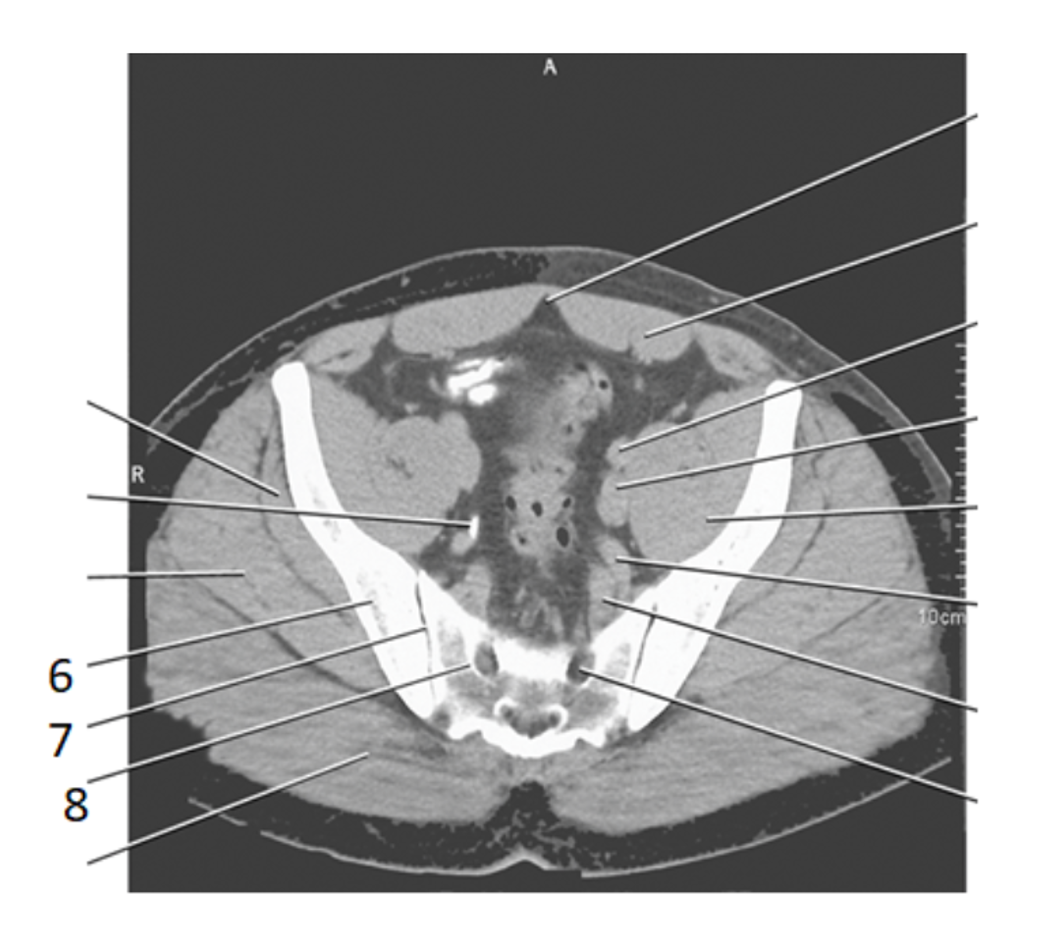

29

pubis

30

ishium

6

ilium

2

sacral prominatory

8

psoas

9

sacram foramen

7

SI joint

28

bladder